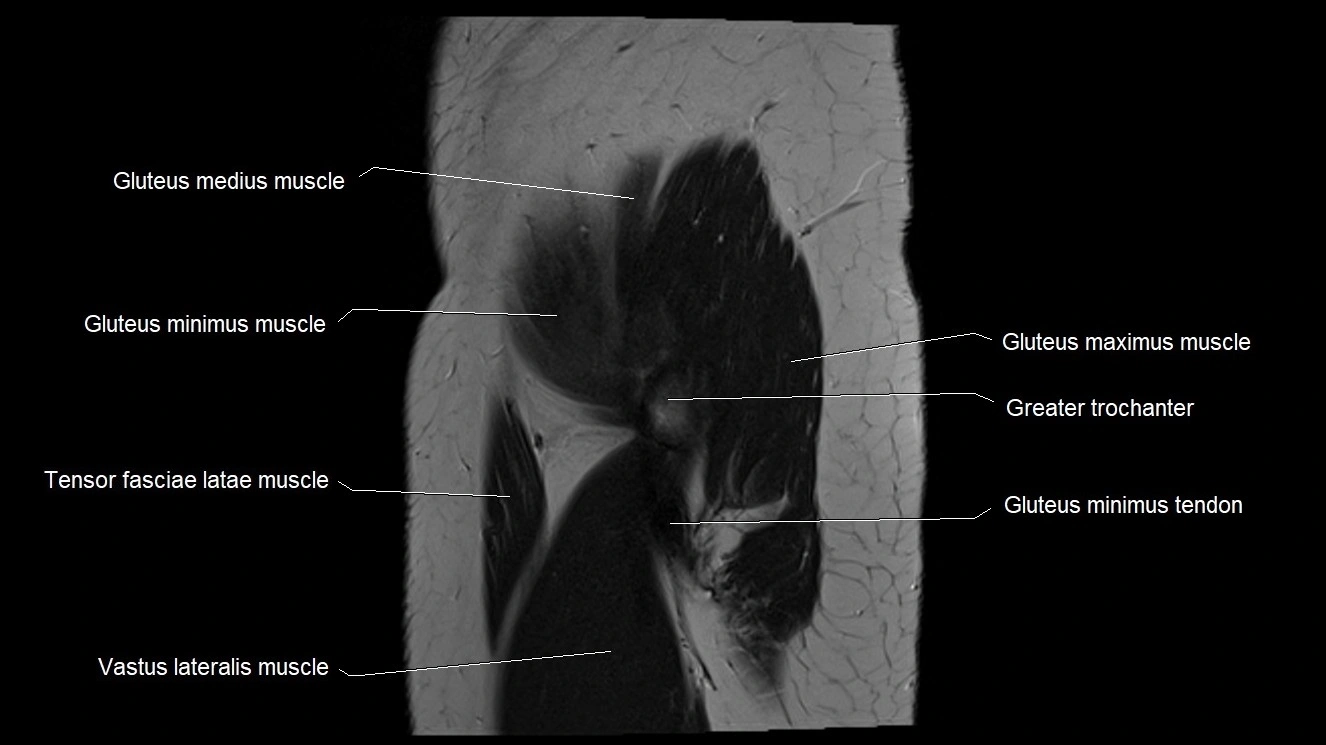

- Gluteus medius muscle

- Gluteus minimus muscle

- Gluteus minimus tendon

- Greater trochanter

- Gluteus maximus muscle

- Iliotibial tract

- Tensor fasciae latae muscle

- Vastus lateralis muscle